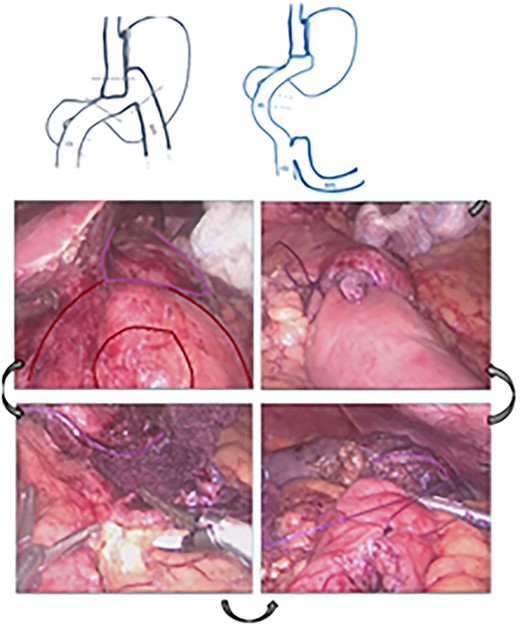

The patient was referred for laparoscopic revision surgery with conversion to RYGB (Fig. 3). In the postoperative period, a torpid evolution included vomiting on various occasions, as well as the detection of ascaris on one occasion. A new upper GI endoscopy showed evidence of permeable gastrojejunal anastomosis and acute inflammatory changes (Fig. 4), and the patient received antiparasitic treatment. Because of persistent symptoms of obstruction, a new surgical intervention was performed, which showed the presence of ascaris in the entero-enteric anastomosis causing its obstruction (Fig. 5). A new anastomosis was performed at a distance of 30 cm from the obstruction (Fig. 6). After the patient showed improvement and tolerated a liquid diet, she received treatment for ascaris and was discharged with good evolution.

Diagram showing the construction of a new entero-enteric anastomosis.